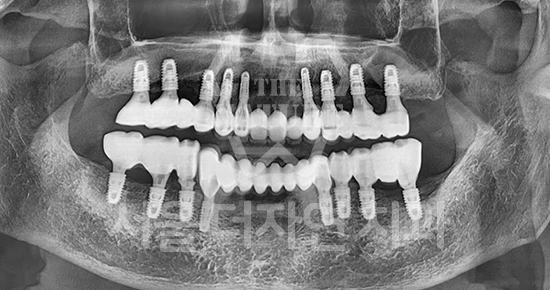

#Full Mouth Implants

-

BEFORE: 2022.12.15

AFTER: 2023.02.23

Full-mouth implants are highly advanced treatment

that require precise upper and lower occlusal harmony.

Patients themselves have proven us to be

a clinic specialized in full-mouth implant surgery.

Full-mouth implants are among the more complex dental procedures. They require careful decision-making, precise diagnosis based on each individual condition, and ongoing postoperative care after placement. With extensive experience in full-mouth implant treatment, Seoul The Nature Dental Clinic can provide systematic planning, placement, and follow-up care. Many patients continue to visit us through recommendations as a trusted clinic for full-mouth implants.